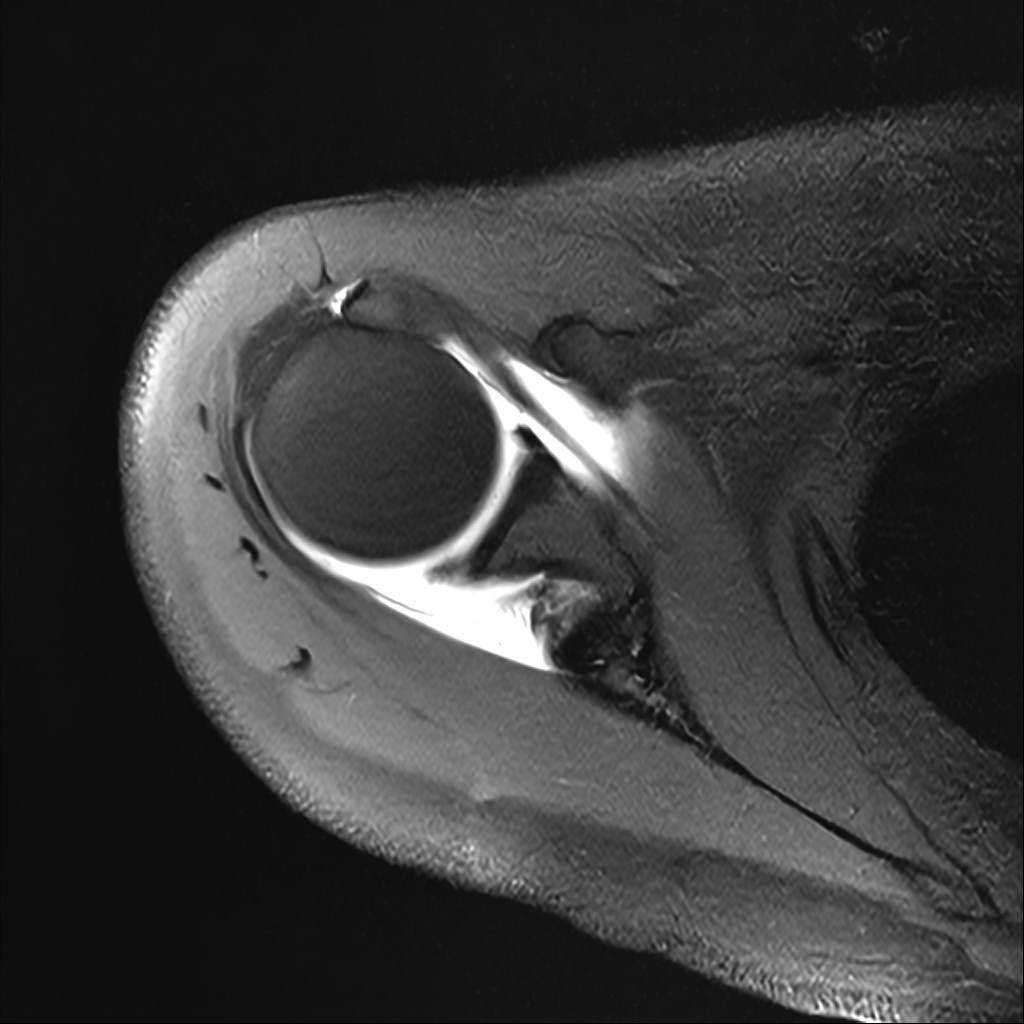

Mri 단면 영상으로 보아 어깨 관절 부위에서 이상 신호가 관찰되고 이는 관절 와순 파열의 가능성을 시사할 수 있습니다.

하지만 이영상만으로 정확한 진단은 불가능하고 정밀한 판단을 위해선 전체 시퀀스와 영상의학과 전문의의 공식판독이 필요합니다 특히 와순 파열은 위치와 동반 병변에 따라 해석이 달라집니다!